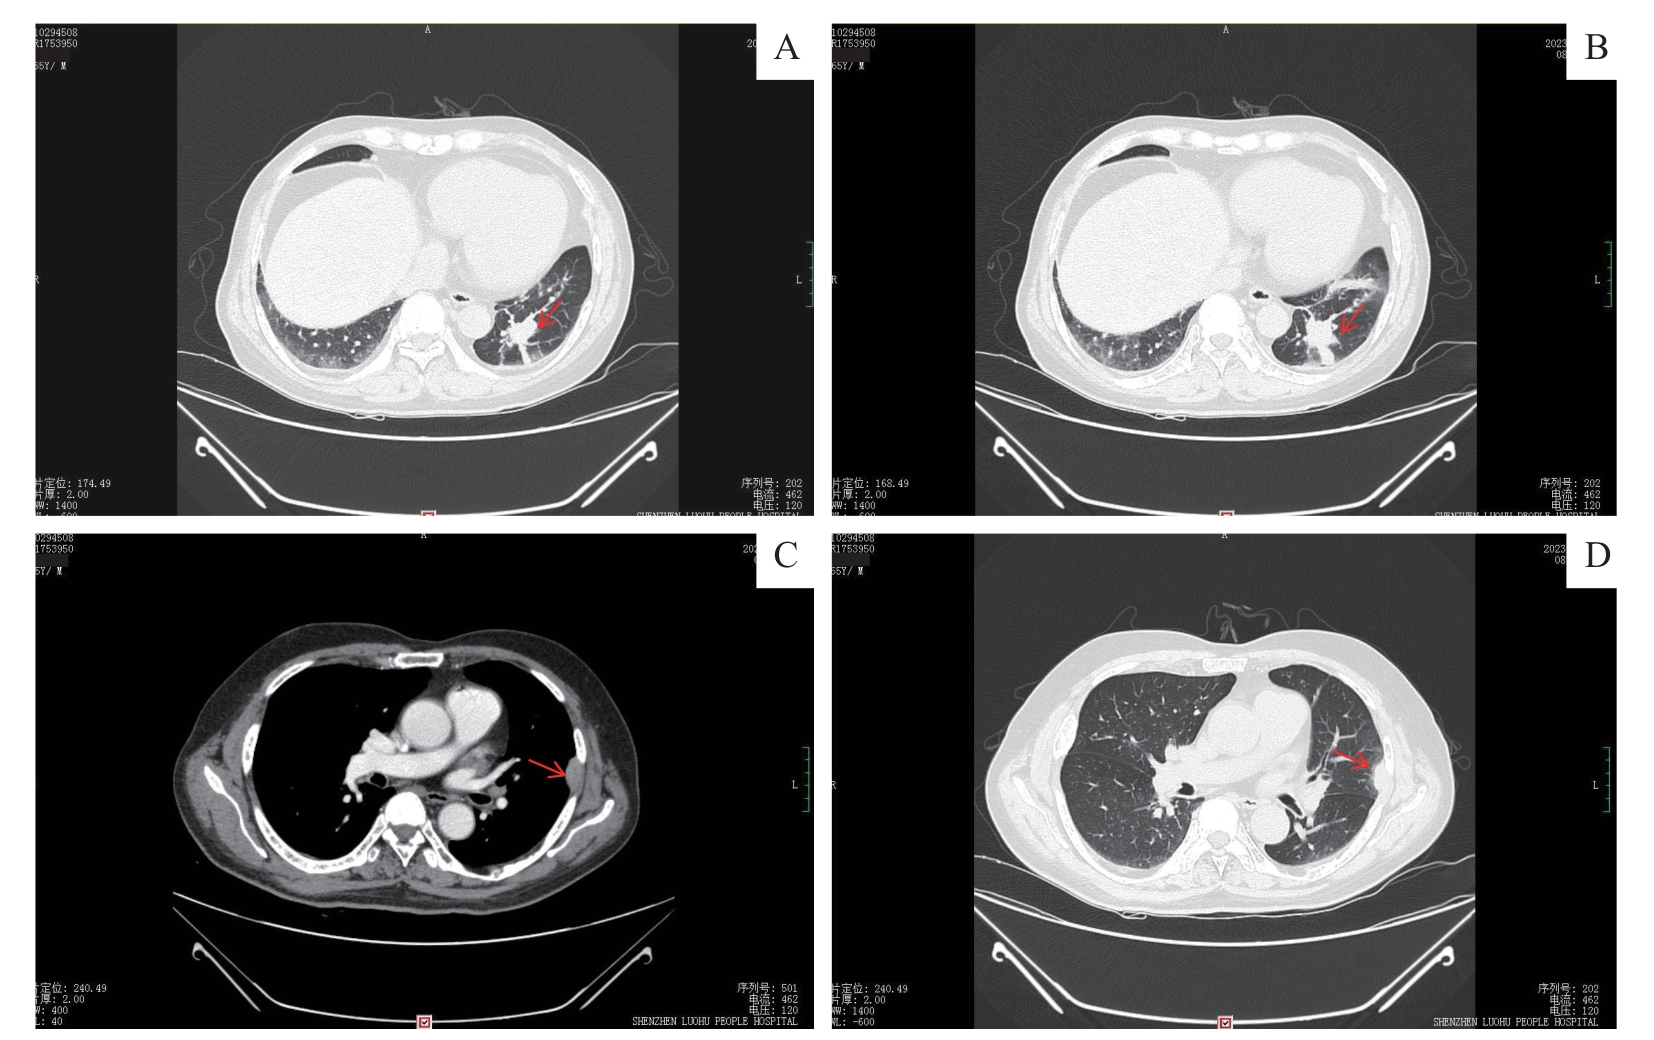

| 图2 胸部增强CT显像 Note: A/B. Two different layers of contrast-enhanced chest CT scans. Multiple elongated strip shadows are visible around the same site, and mild sustained enhancement is visible on contrast-enhanced scans (arrow). C. Contrast-enhanced chest CT showing a chest wall mass (arrow) at the mediastinal window level. D. Contrast-enhanced chest CT showing a chest wall mass (arrow) at the lung window level. |

| Fig 2 Contrast-enhanced chest CT scans |